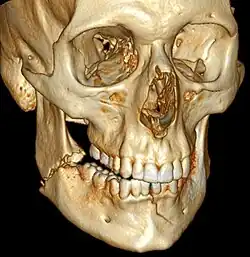

3D computed tomographic image of a mandible fracture in two places. One is a displaced right angle fracture and the other is a left parasymphyseal fracture.

Computed tomography

Computed tomography is the most sensitive and specific of the imaging techniques. The facial bones can be visualized as slices through the skeletal in either the axial, coronal or sagittal planes. Images can be reconstructed into a 3-dimensional view, to give a better sense of the displacement of various fragments. 3D reconstruction, however, can mask smaller fractures owing to volume averaging, scatter artifact and surrounding structures simply blocking the view of underlying areas.